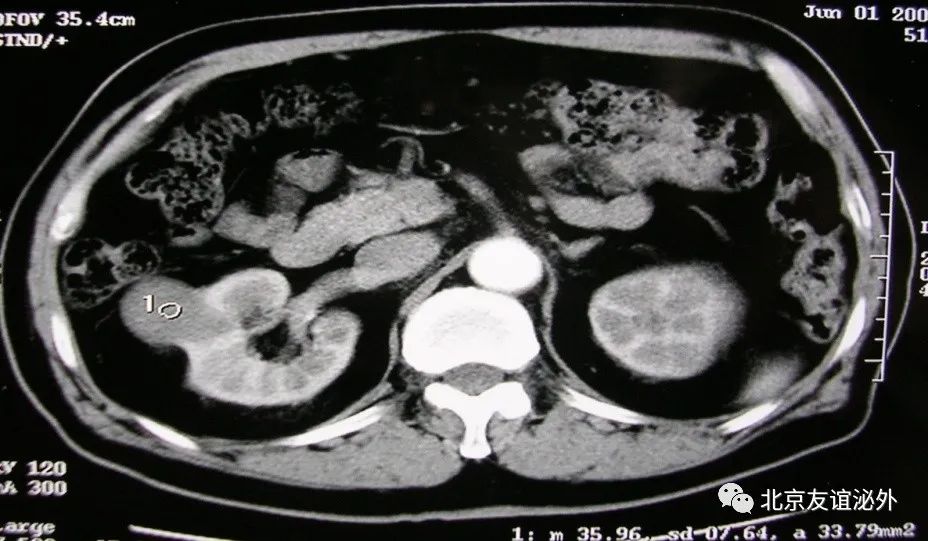

图4. Bosniak IIF级良性囊肿(囊肿伴乳头状瘤)